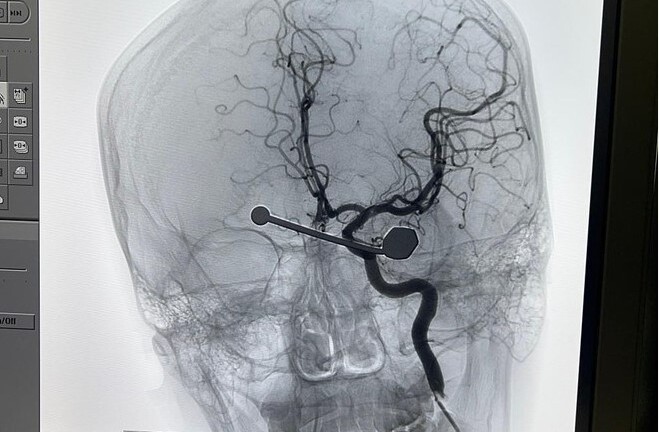

Tiếp nhận bệnh nhân, các bác sĩ kích hoạt quy trình cấp cứu đột quỵ. Kết quả chụp MRI sọ não cho thấy bệnh nhân bị nhồi máu não bán cầu trái, tắc động mạch não giữa trái. Do đây là tình trạng đột quỵ rất nặng nên người bệnh nhanh chóng được can thiệp tái thông động mạch máu não giữa trái.

Sau khi được can thiệp tái thông động mạch máu não giữa trái, bệnh nhân đã có thể cử động tay và chân phải. Người bệnh được xuất viện về nhà sau 4 ngày nhập viện.